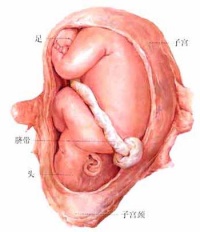

受精后约一周,胚泡植入增厚的子宫内股中,这就称为妊娠。胚泡不断通过细胞分裂和细胞的分化而长大,分成了两部分。一部分是胚胎本身将来发育成胎儿;另一部分演变为胚外膜,最重要的是羊膜、胎盘和脐带,胎儿通过胎盘和母体进行物质交换。

受精后约一周,胚泡植入增厚的子宫内股中,这就称为妊娠。胚泡不断通过细胞分裂和细胞的分化而长大,分成了两部分。一部分是胚胎本身将来发育成胎儿;另一部分演变为胚外膜,最重要的是羊膜、胎盘和脐带,胎儿通过胎盘和母体进行物质交换。